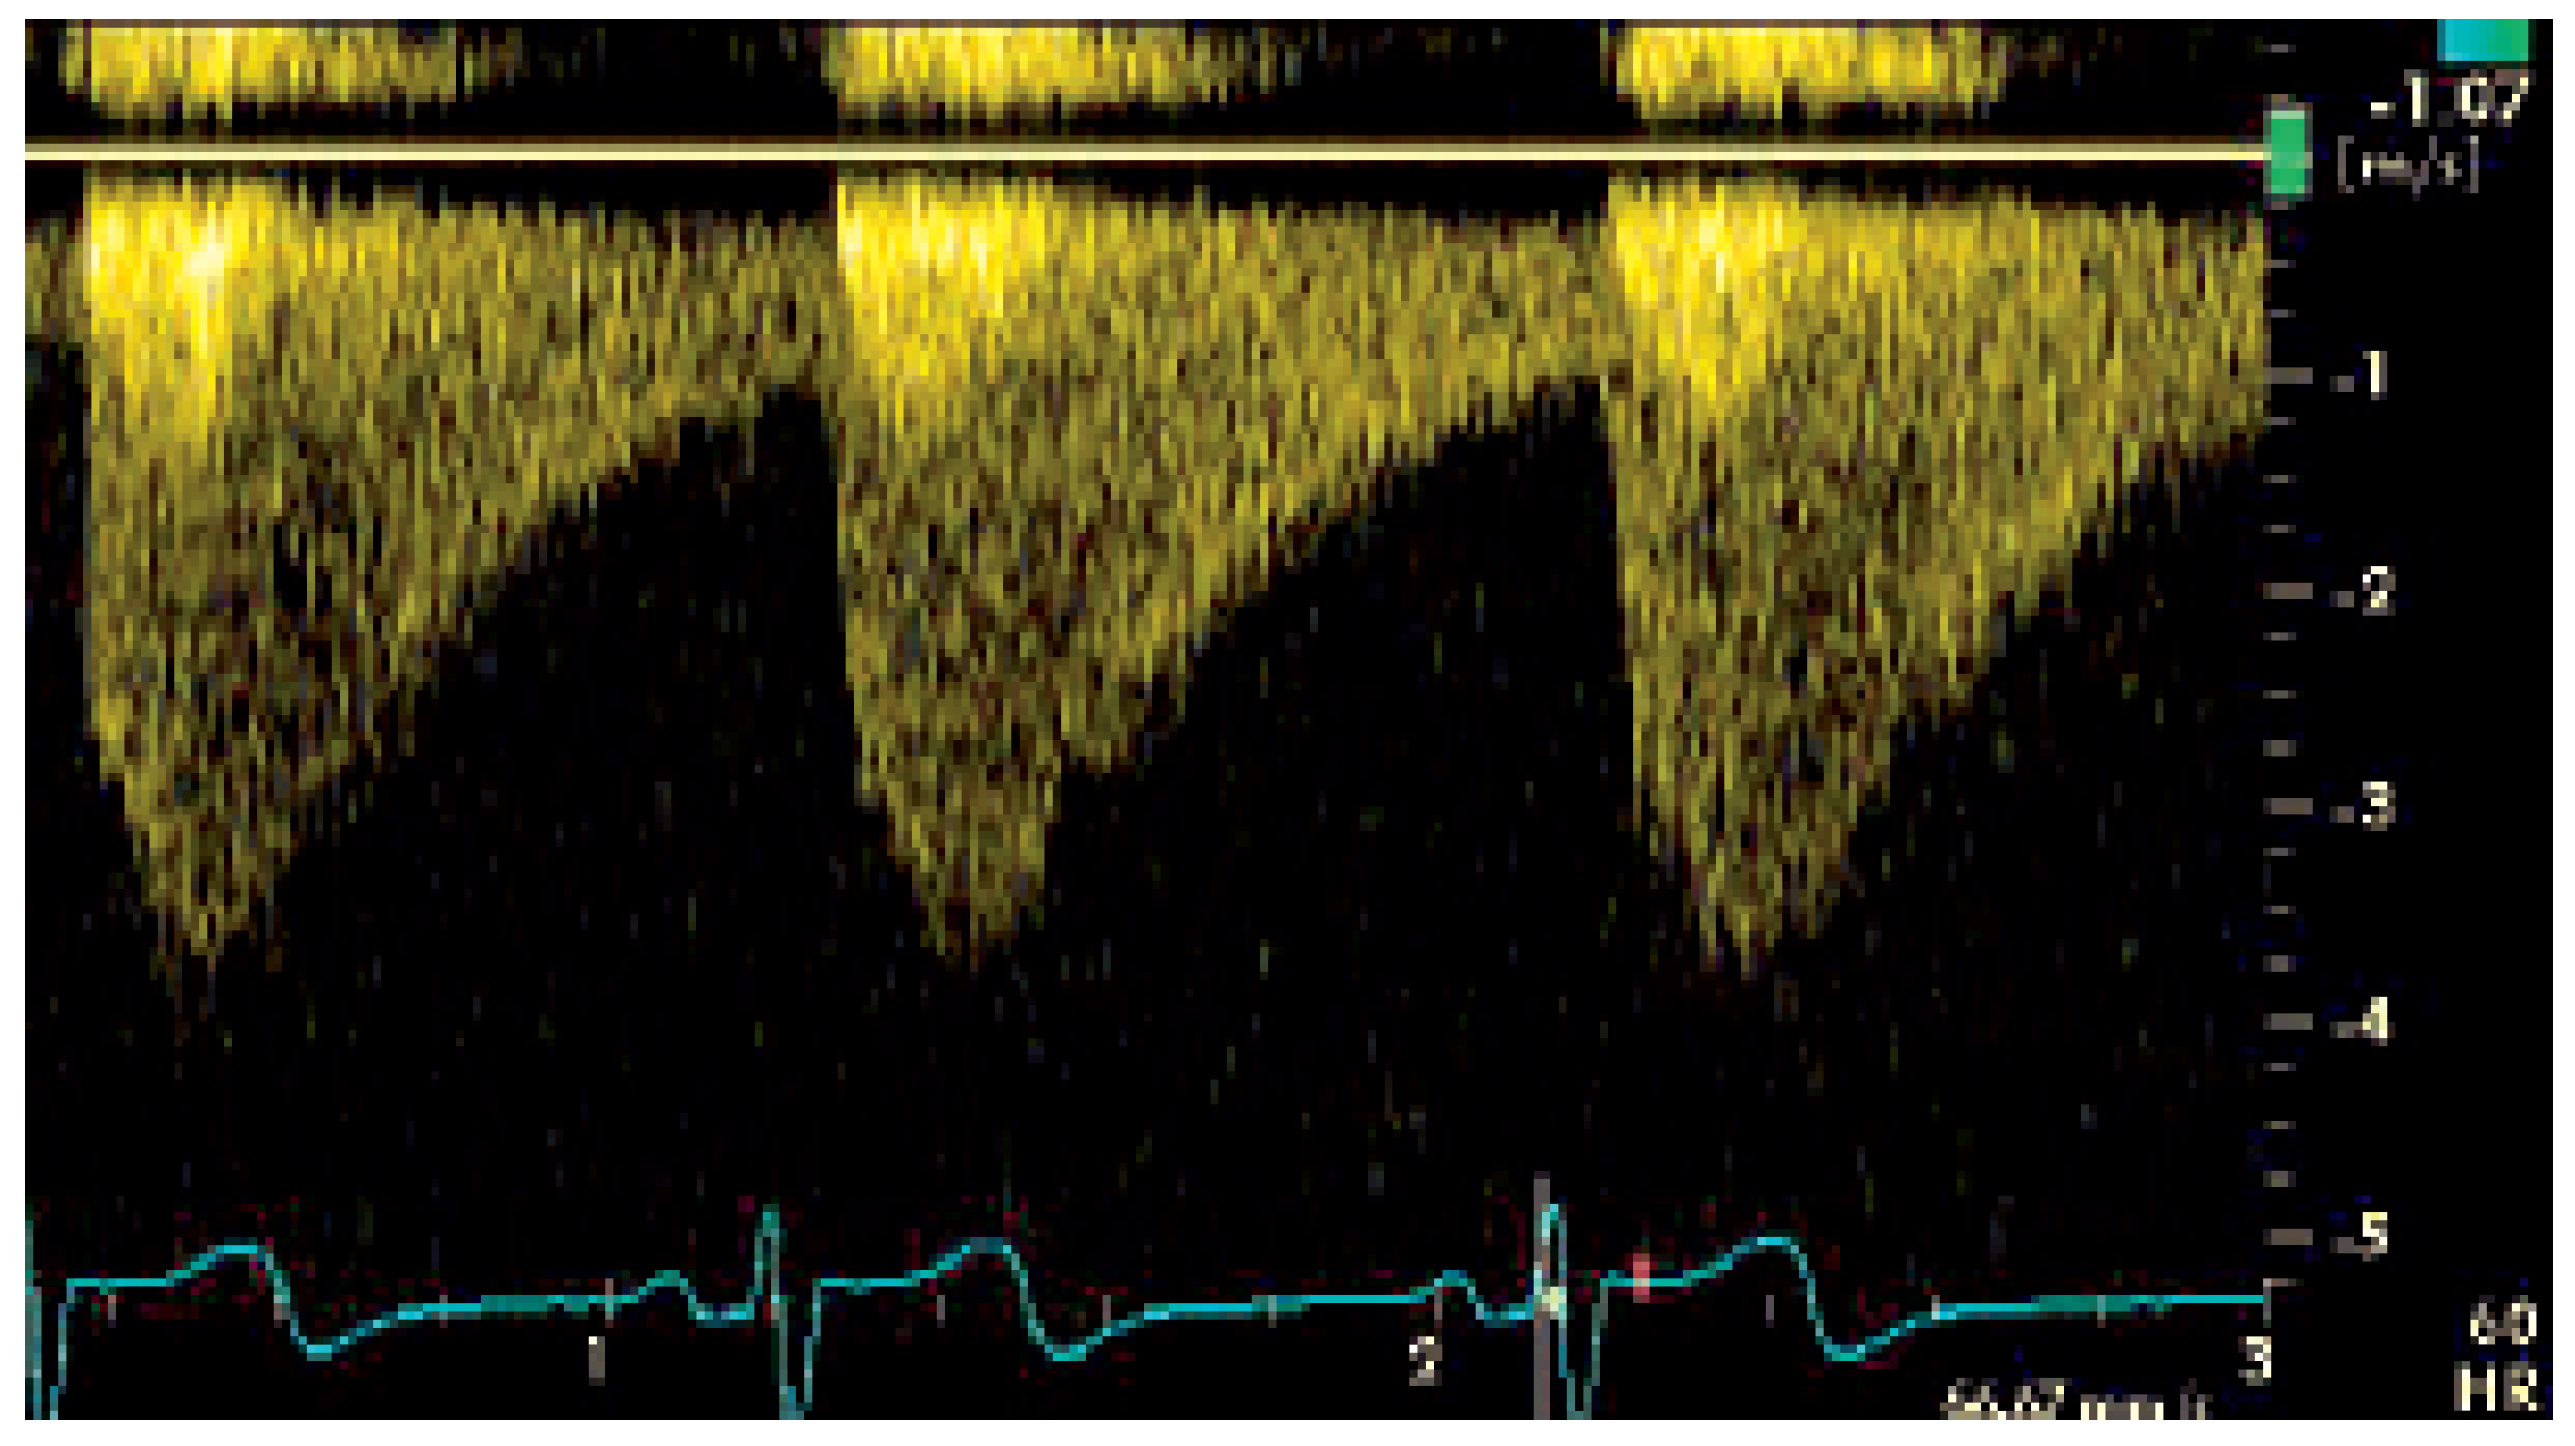

Die katheterinterventionelle Therapie gestaltete sich als komplikationslose Stent-Implantation mit Erweiterung des Aortenlumens im Bereich der AIS von knapp 1,4 mm auf 12 mm und entsprechender Reduktion des Druckgradienten von initial 40 mm Hg auf 5 mm Hg (Figure 3).

Figure 3. Angiographische Darstellung der hochgradige Stenose (A) und postinterventionelles Resultat mit korrekter Position des Stentes und vollständiger Behebung der Einengung (B).